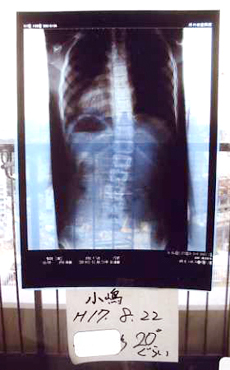

症例4)

初診15度でしたが体操3ヶ月後で0度に改善、左右肋骨のバランスも改善。

小学1年 6歳 女子 学校検診で発見

2006年4月24日 整形外科へ受診、15度とされ診断6ヵ月後に経過を診るとのこと

2006年4月30日 レントゲンを持参され当院へ。

低度数のため大塚式鍛錬体操を指導し、自宅で毎日していただくことをお願いした。

2006年7月19日 整形外科へ再検診0度、前は側湾ではなかったのではと話す。

改善後のレントゲンを持参されボディ写真を記録、体操効果が継続されていることを確認。大塚整体治療院通院終了とした。自宅での体操は継続されるようにお話した。

初診

体操2週間後

体操3ヵ月後

2006年4月30日

2006年5月13日

2006年7月22日

大塚式鍛錬

体操後

15度

0度

体操2週間後の体型が、1ヶ月後、2ヵ月後も維持されており3ヵ月後のレントゲン検診で0度となり改善されました。

この改善は母親の毎日の指導と彼女の努力をほめてあげなければいけない。 大塚式鍛錬体操は経過観察という放置療法ではなく積極的改善療法です。

自然治癒力というが放置ではなく、よい習慣をつけさせることが治癒力を発揮された例である。